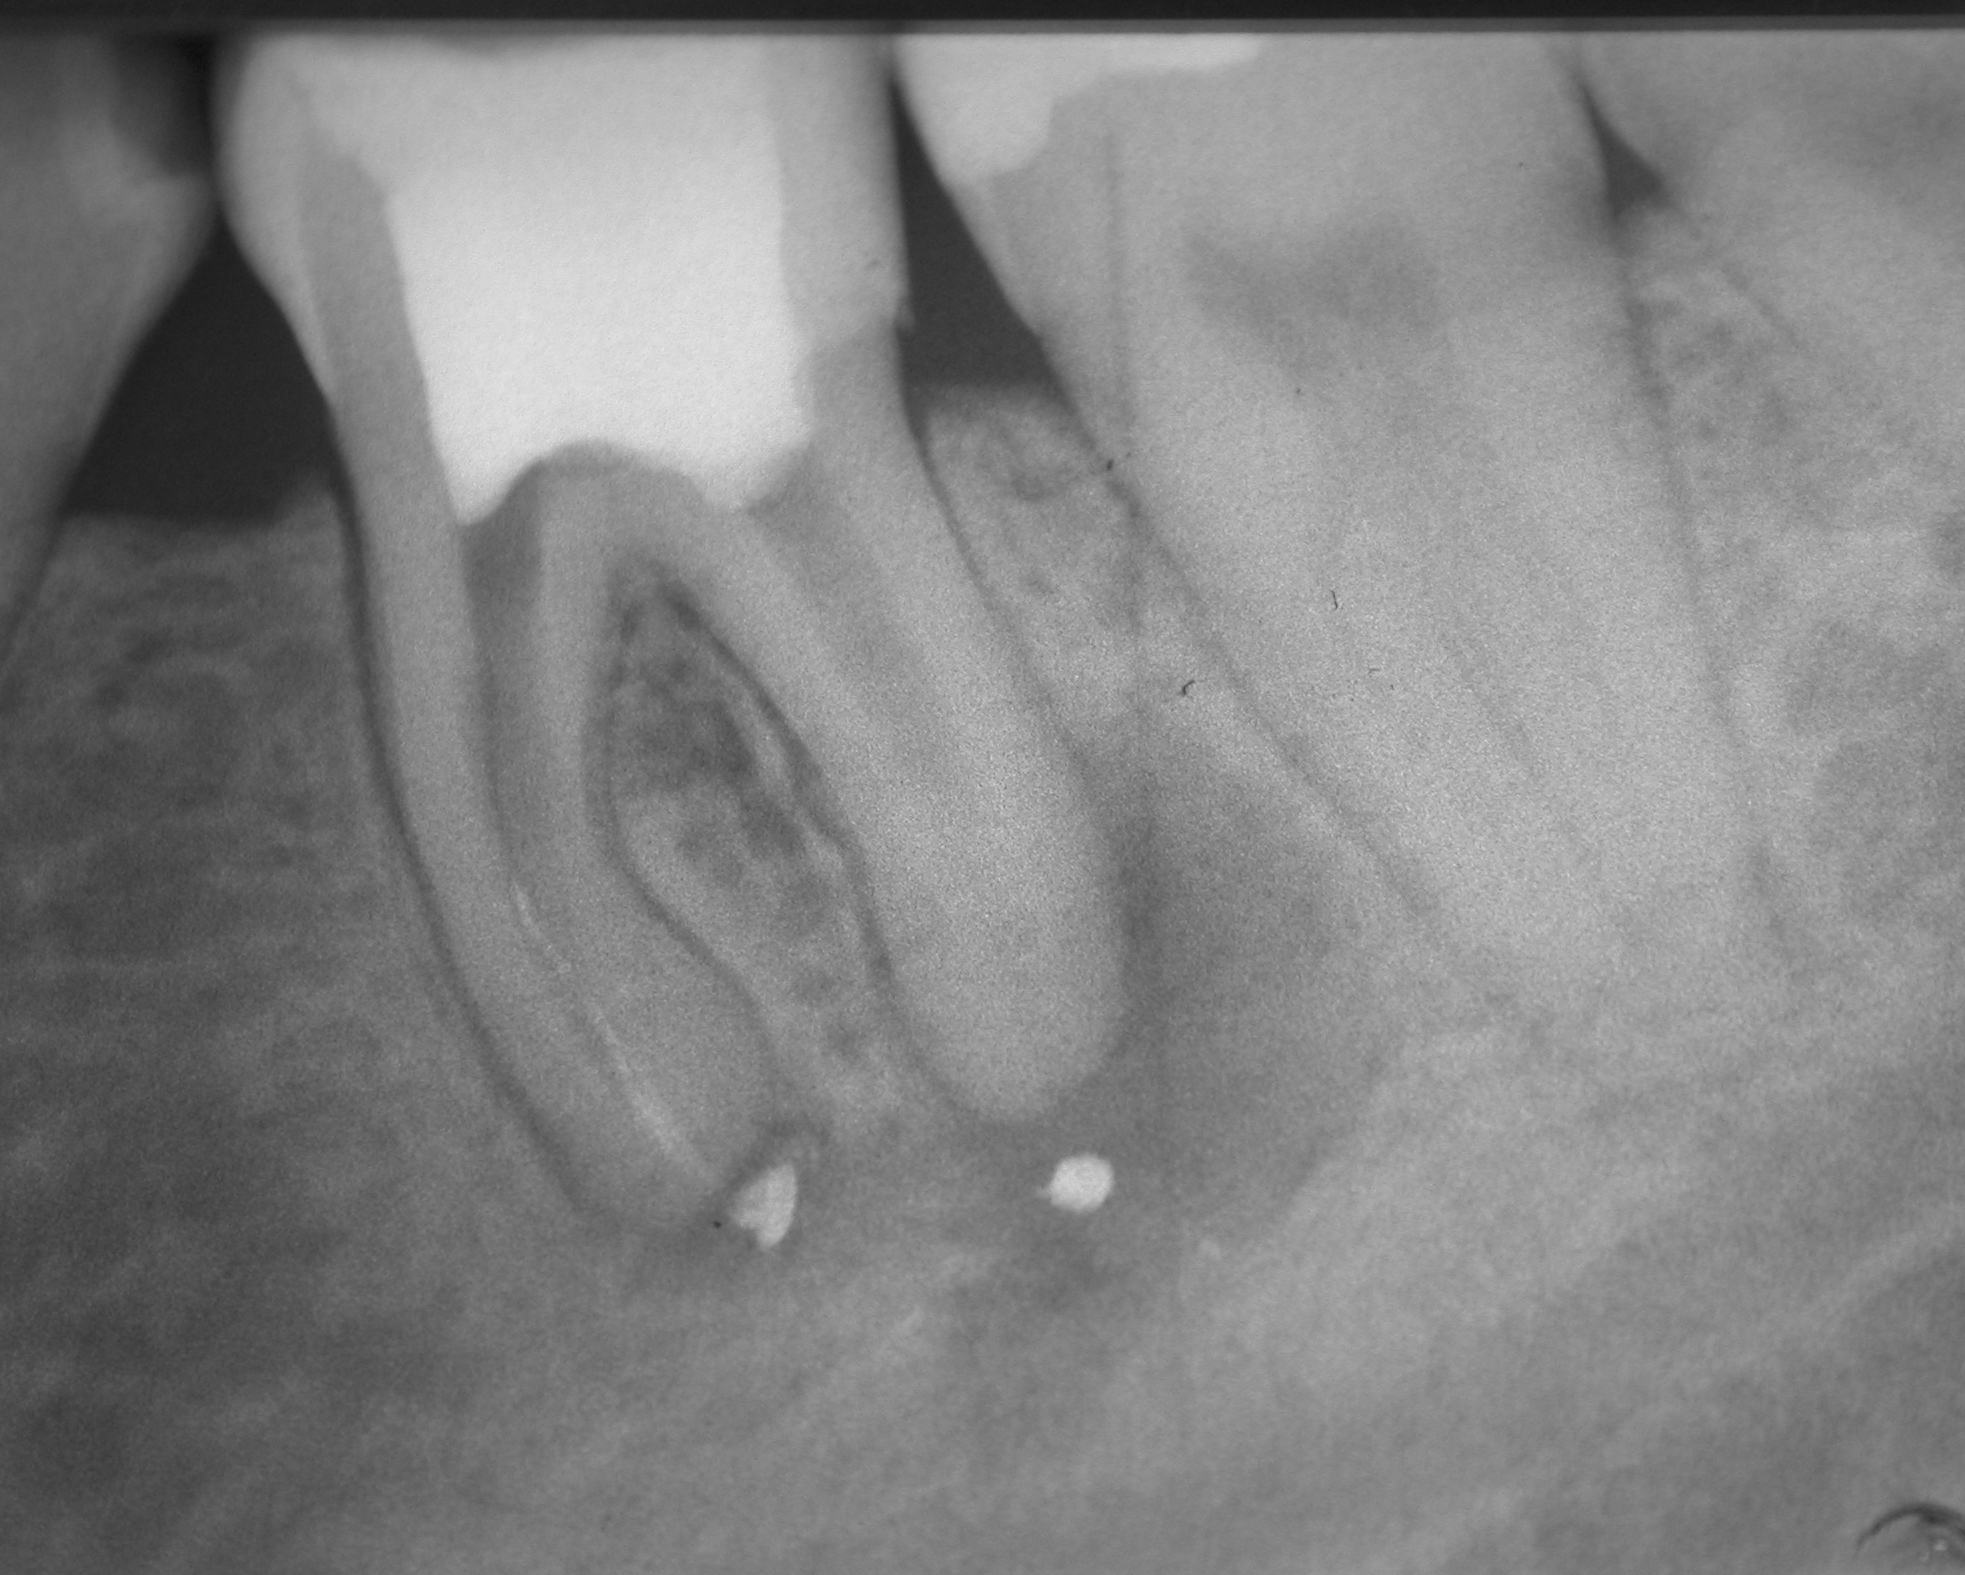

Fast 15 Jahre im Recall – Zahn 36 (2)